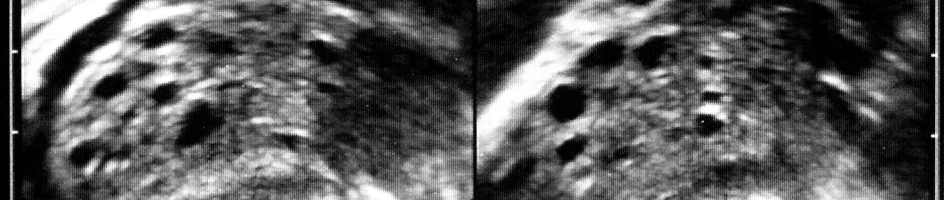

- typische Ausbildung eines polycystischen Ovars im Rahmen der Ultraschalluntersuchung